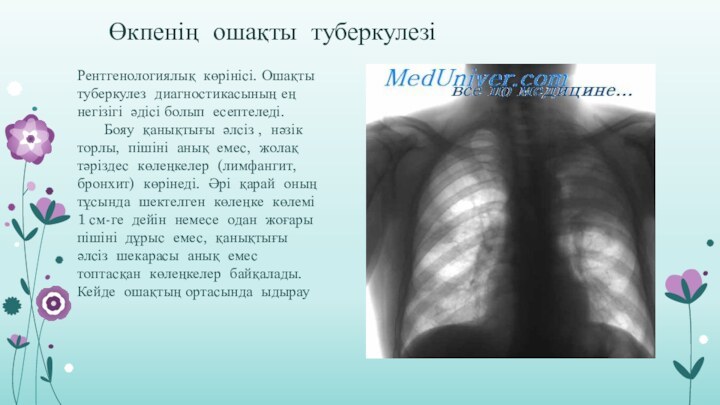

Симптомы и лечение инфильтративного туберкулеза легких